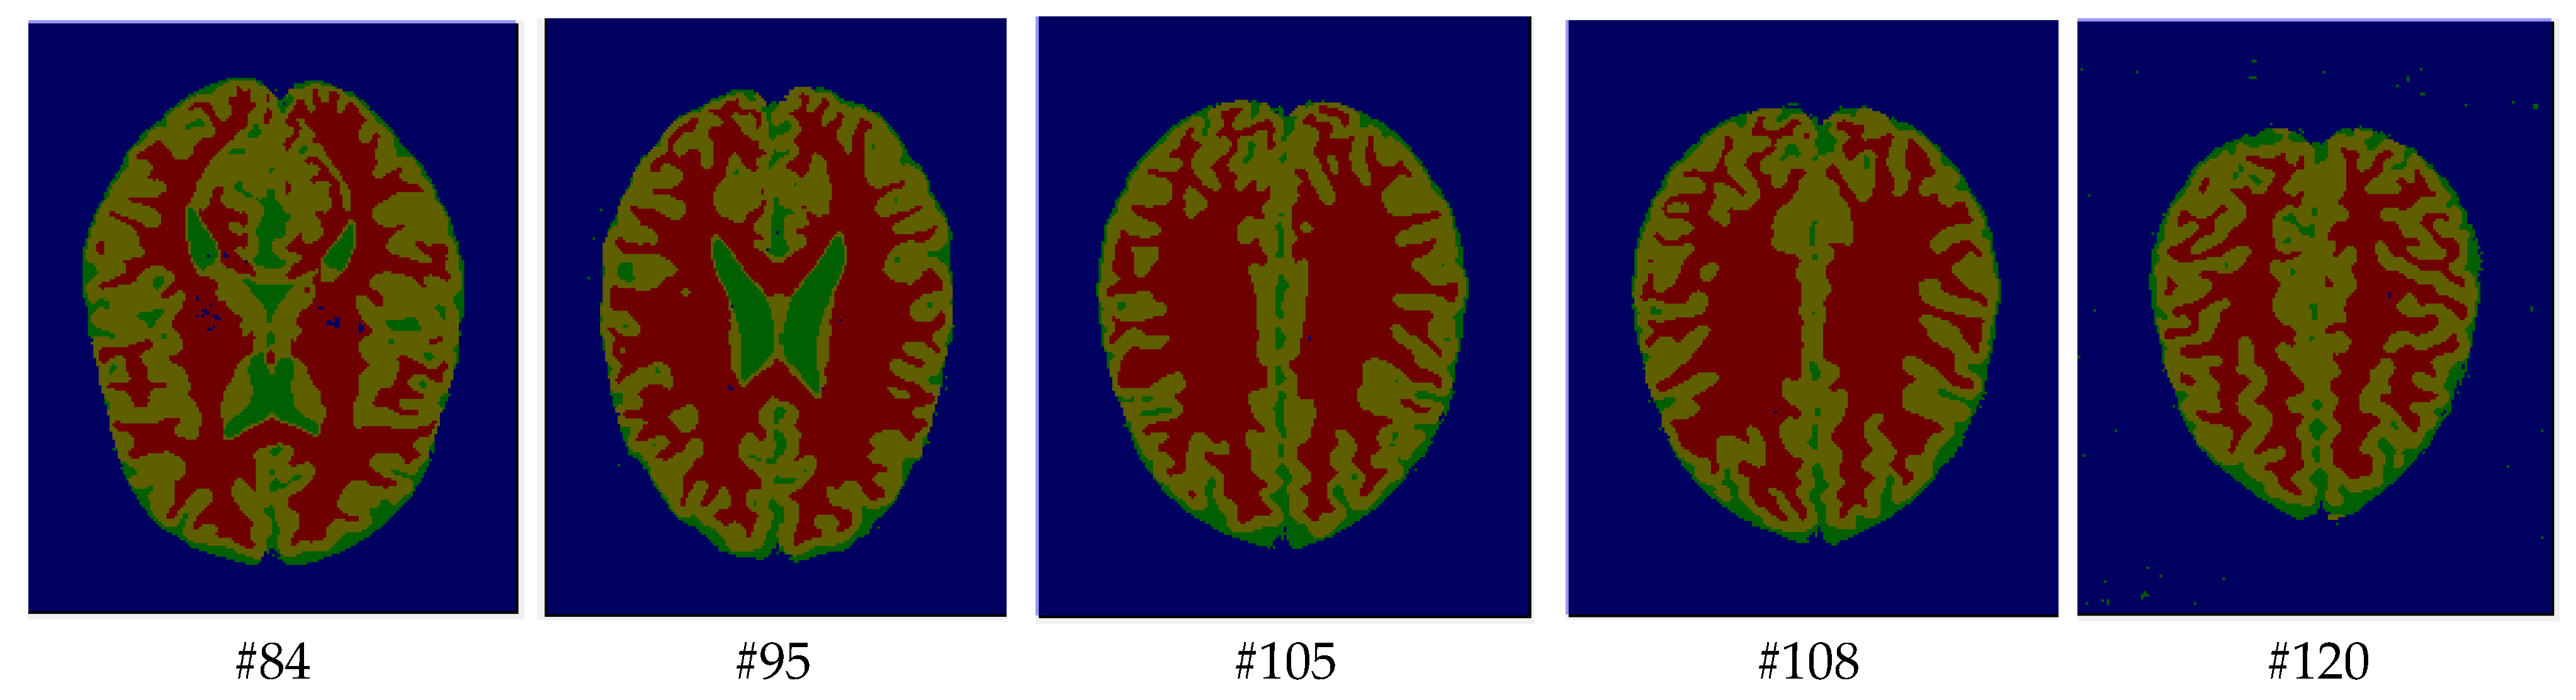

As mentioned before, the images of the first five datasets in Table 3 were used to evaluate the performance of the HMRF-WOA. Figure 1, Figure 2, Figure 3, Figure 4 and Figure 5 show some slices of a T1-weighted image (slices: 84, 95, 105, 108, 120). These brain images correspond to the slices under different types of conditions, such as database type, dimension image, noise level, intensity non-uniformity level, and slice thickness (mm). In Table 1, rows 1 to 5 summarize the parameters of Figure 1, Figure 2, Figure 3, Figure 4 and Figure 5, respectively. Figure 6 represents the ground truth segmentation of slices 84, 95, 105, 108, and 120. In this figure, each column contains the three tissues, GM, WM, and CSF, of each slice. Figure 7, Figure 8, Figure 9, Figure 10 and Figure 11 show the segmentation results, where the four tissues (BG, GM, WM, and CSF) are shown with different colors. The yellow, red, and green colors represent the segmented regions of GM, WM, and CSF, respectively. As we can also see from these figures, the resulting segmented images in Figure 7, Figure 8, Figure 9, Figure 10 and Figure 11 are almost close to the initial images in Figure 1, Figure 2, Figure 3, Figure 4 and Figure 5.

The qualitative analysis provides a visual representation of the segmentation approaches. The visual comparison of the resulting images using the HMRF-WOA appears to be more similar to the reference image (ground truth), where Figure 1, Figure 2, Figure 3, Figure 4 and Figure 5 show the GM, WM, and CSF tissue regions of the reference image with higher values of noise levels (3, 5, 7, and 9%) and intensity non-uniformity levels (20, 40%), whereas Figure 7, Figure 8, Figure 9, Figure 10 and Figure 11 show the subject images obtained using the proposed technique. However, this result shows that with higher values of noise and intensity non-uniformity, the algorithm, with its hyperparameters, is able to segment the tissue regions correctly.

Figure 7. Segmentation results of the slices illustrated in Figure 1.